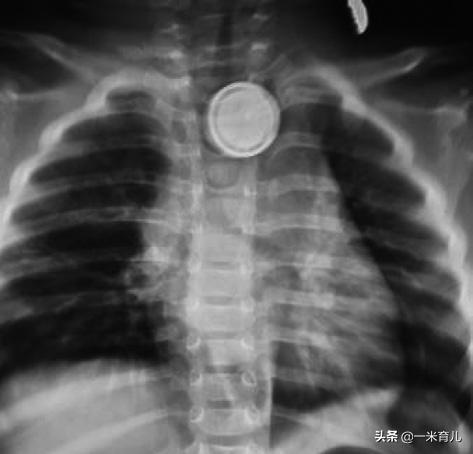

- 纽扣电池变老虎?

越来越多的玩具、家用电器中使用纽扣电池。据统计,儿童吞食纽扣电池的发生率约为 6/1000000~15/1000000。

因纽扣电池含有重金属及化学复合物,对食道壁具有较强的腐蚀性,儿童吞食纽扣电池后,能对食管造成阻塞和碱性化学物质烧伤,极易导致食管穿孔、气管食管瘘、大出血、食管狭窄等严重并发症。

一旦发生儿童误食纽扣电池,应尽快送医院诊治,制定适宜的治疗方案对孩子的预后十分重要。

有些直径较小的纽扣电池可通过胃肠道,几天后随粪便排出体外;但如果电池直径超过20毫米,则可能会嵌顿在食道中,需要快速诊断和迅速取出。

儿童吞食纽扣电池临床特征

纽扣电池食管异物已成为全球性问题,每一个家庭都应该做好对纽扣电池的管理,与孩子一起了解纽扣电池的危害,预防意外情况的发生。